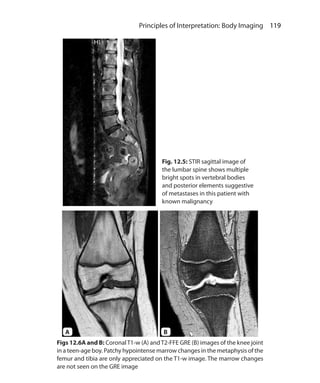

suppressed and contrast shortens T1

of tissues that uptake the contrast

5. Can be used in postcontrast imaging